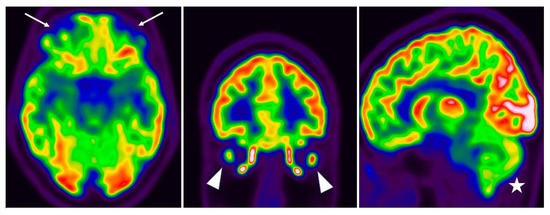

Persistent 18F-FDG Brain PET Fronto-Temporal Hypometabolism and Cognitive Symptoms Two Years after SARS-CoV-2 Infection: A Case Report

2. Case Description

3. Discussion

- Guedj, E.; Campion, J.Y.; Dudouet, P.; Kaphan, E.; Bregeon, F.; Tissot-Dupont, H.; Guis, S.; Barthelemy, F.; Habert, P.; Ceccaldi, M.; et al. 18F-FDG brain PET hypometabolism in patients with long COVID. Eur. J. Nucl. Med. 2021, 48, 2823–2833. [Google Scholar] [CrossRef]

- Dressing, A.; Bormann, T.; Blazhenets, G.; Schroeter, N.; Walter, L.I.; Thurow, J.; August, D.; Hilger, H.; Stete, K.; Gerstacker, K.; et al. Neuropsychologic Profiles and Cerebral Glucose Metabolism in Neurocognitive Long COVID Syndrome. J. Nucl. Med. 2021, 63, 1058–1063. [Google Scholar] [CrossRef]

- Blazhenets, G.; Schroeter, N.; Bormann, T.; Thurow, J.; Wagner, D.; Frings, L.; Weiller, C.; Meyer, P.T.; Dressing, A.; A Hosp, J. Slow but evident recovery from neocortical dysfunction and cognitive impairment in a series of chronic COVID-19 patients. J. Nucl. Med. 2021, 62, 910–915. [Google Scholar] [CrossRef]

- Ferrucci, R.; Cuffaro, L.; Capozza, A.; Rosci, C.; Maiorana, N.; Groppo, E.; Reitano, M.R.; Poletti, B.; Ticozzi, N.; Tagliabue, L.; et al. Brain positron emission tomography (PET) and cognitive abnormalities one year after COVID-19. J. Neurol. 2023, 270, 1823–1834. [Google Scholar] [CrossRef]